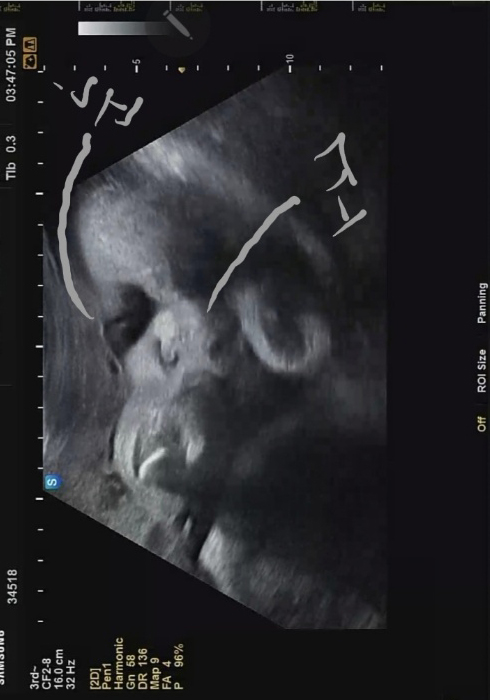

차츰 주수가 늘어날수록 초음파 영상에 꽉 차는 까꿍이 모습. 이제는 양수가 줄어들면서 태아가 차지하는 공간이 많아지는 시기기 때문에 더 그러는 것 같다. 제한된 공간에서 손을 웅크리고 있는 까꿍이. 역시나 얼굴보기 힘들었지만 잠깐이나마 가까스로 언 듯 보이는 까꿍이 얼굴이 너무 반갑다.

확실히 예전에는 얇상했다면, 이번 초음파에서는 볼살과 얼굴이 통통해졌음을 느낄 수 있었다..ㅋㅋ 귀여워😍🧡💕